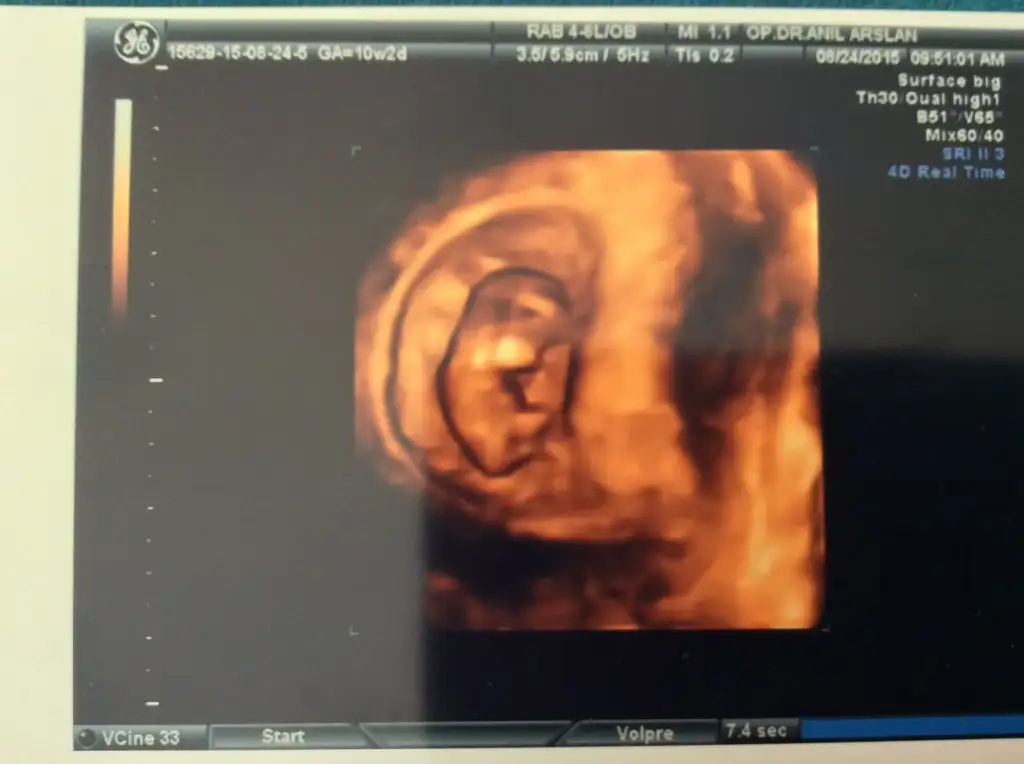

Eki Görüntüle 1613851 kızlarr bakın bebişin remini atabilmeyi başardım:):)

Kıza benziyo :) nub denen bir yöntem varmış galiba forumda okudum ultrasonda popo bölümündeki iki çıkıntı birbirine paralelse kız olurmuş :)Eki Görüntüle 1613851 kızlarr bakın bebişin remini atabilmeyi başardım:):)